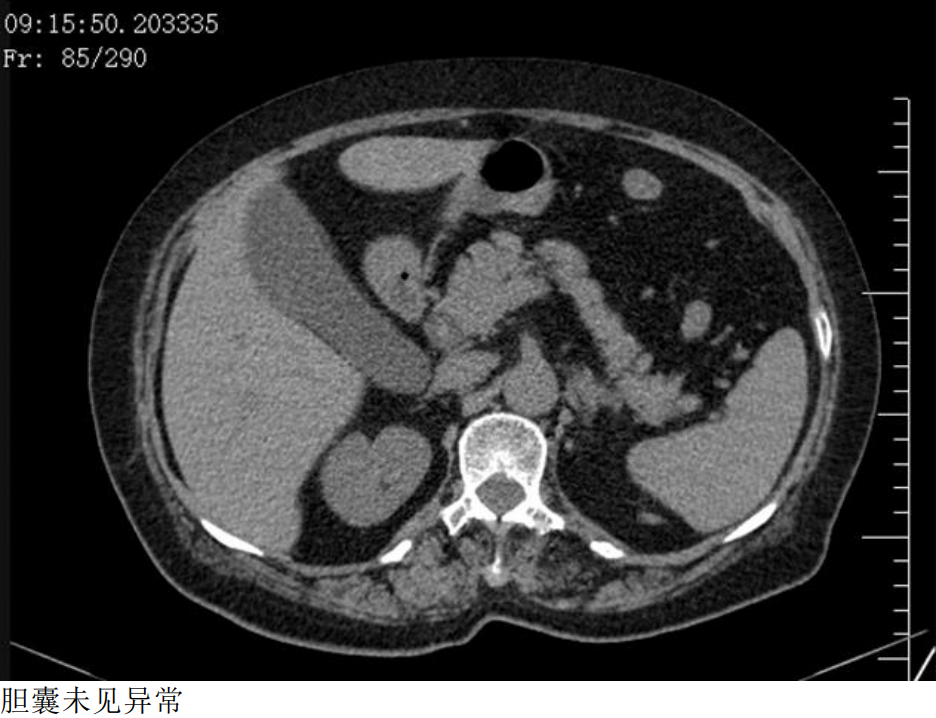

二、早上9:15,CT平扫

DWI胆囊内病变呈高信号,ADC值下降,提示弥散受限。 LAVA-FLEX四像图:水像病变呈等低信号,脂肪像低信号,同反相位未见显著信号改变,提示病变不含大量脂肪成分。 小朋友,你是否也有很多问号? 超声,CT都提示胆囊未见异常。 MR发现胆囊里面这么大一坨东西。 它是什么,它来自哪里,它会去向何方? 没有伪影的MR是不正常的,机器问题,参数问题? 四、晚上18点,超声复查